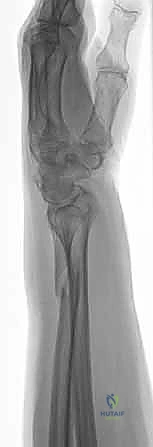

صورة طبية توضح كسر الناتئ الإبري

صورة لكسر في رأس الزند

توضيح لكسور الجزء الكردوسي الكردوسي

استخدام الأشعة السينية في التشخيص

1. الأشعة السينية (X-rays): بوضعيات متعددة (أمامية خلفية، وجانبية دقيقة). الوضعية الجانبية الحقيقية (True Lateral) حاسمة لاكتشاف أي خلع جزئي في المفصل (DRUJ).